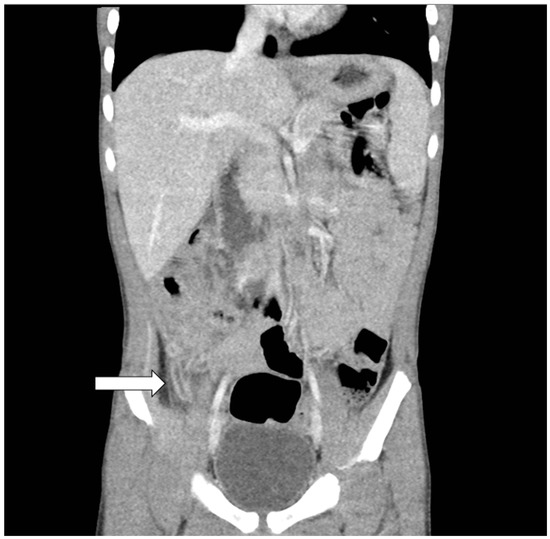

2. Case Report